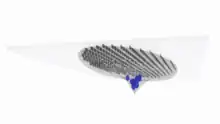

The lens capsule is a transparent membrane that surrounds the entire lens. The capsule is thinnest at the posterior pole with approximate thickness of 3.5μm. Average thickness at the equator is 7μm.[5][9] Anterior pole thickness increases with age from 11-15μm. The thickest portion is the annular region surrounding the anterior pole. This will also increases with age (from 13.5-16μm).[10] The ligaments suspending the lens form attachments in the equatorial area and more so just to the front and back of the equator.[11] There are tens of thousands of these ligaments in a mouse lens and for the most part they appear to connect directly to the lens capsule.[12]

As the lens grows throughout the life of most vertebrates the capsule is required to grow as well.[13] As shown in the accompanying micrographs and diagrams some ligament anchors have associated cells where they connect to the lens capsule. These cells have periodic cellular processes penetrating the capsule.

The structures in the images are consistent with the laying down of new capsular material required for growth. Even though the capsule is a highly elastic structure,[14] it contains no elastic fibers. Elasticity is because of the thick lamellar arrangement of the collagen fibers.[10]